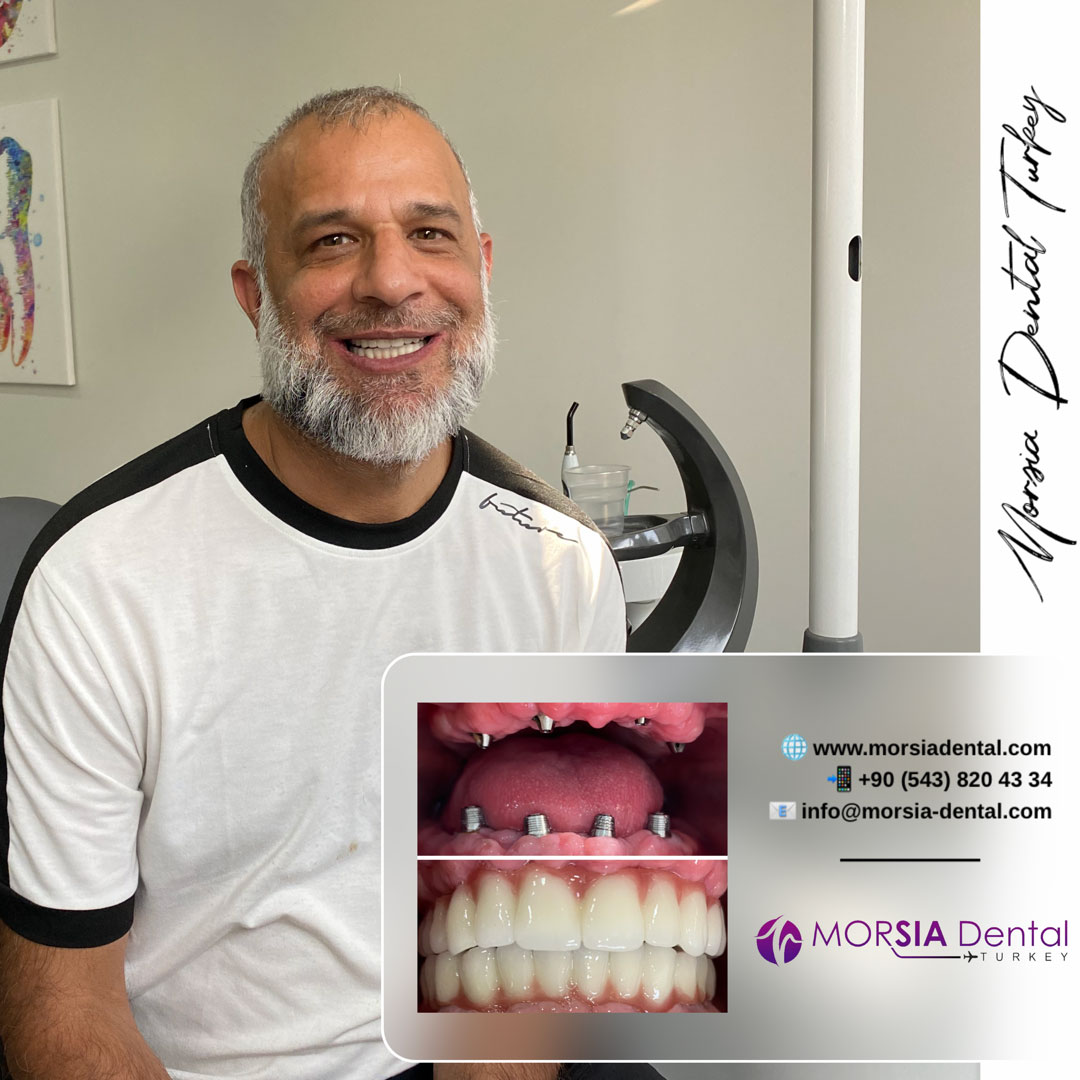

Ceux qui nous ont choisis

Ceux qui nous ont choisis

Découvrez les sourires transformés chez Morsia Dental.

Ceux qui nous ont choisis